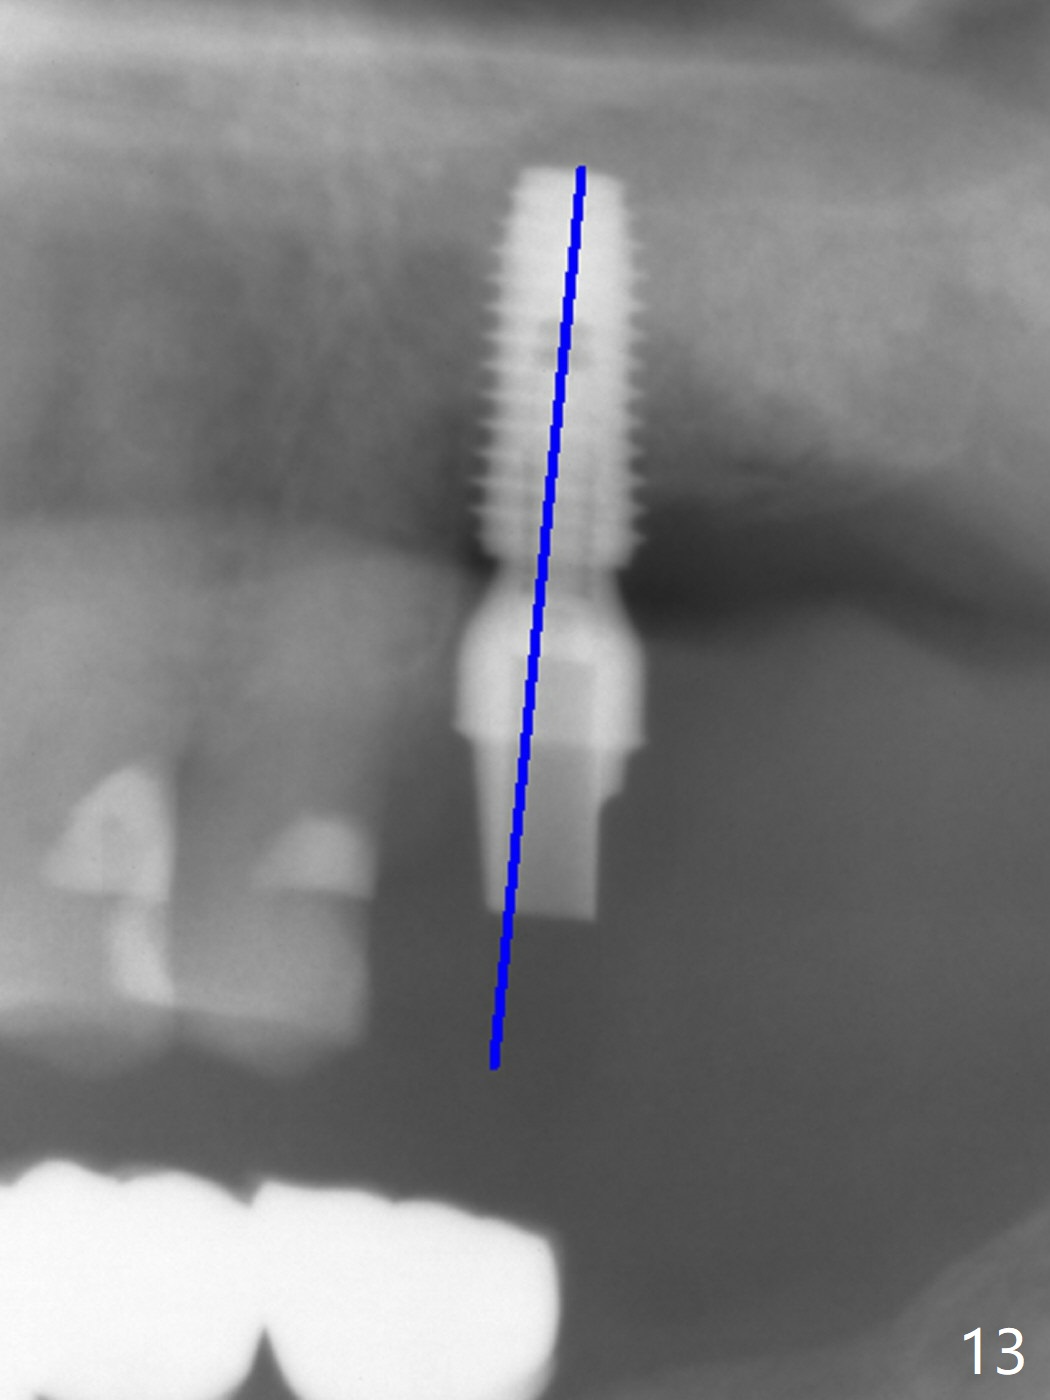

The septum is found to be pointed after extraction of the tooth #14 (Fig.1 *). The septum is flattened with Rongeur (Fig.2 *) prior to osteotomy. Because of interference of the mesial bone (Fig.3 *), osteotomy does not reach the depth with use of stopper. Without the latter, a 5x11.5 mm implant barely penetrates the sinus floor (Fig.4 (no postop nasal hemorrhage)). Also due to the mesial bone interference, a 6.5 mm abutment is not seated. Finally a 5.5x7(5) mm abutment is placed for an immediate provisional. Periodontal dressing is applied to cover the buccal repaired gingiva (Fig.5 *). There is minimal thread exposure after removal of the provisional nearly 2 months postop (Fig.6). The provisional does not return for easy self cleansing. In fact this is not an easy task, because of the posterior position (Fig.8 (after Piezo scaling)). The distal implant remains exposed; the abutment is removed and a healing screw is placed (Fig.9). The implant should have been subcrestal distally (Fig.7 <, nearly 3 months postop). One month later, the implant seems to be buried (Fig.10). The straight abutment is changed to an angled one (4.5 x15 degree A (5) mm) before impression retake (Fig.11,12 (<, dashed line: access hole)). The implant should have been placed more mesial (Fig.13). Surgical guide is needed. There is no implant exposure clinically or in CBCT sections 1 year 2 months post cementaton (Fig.14), although 3 D image suggests missing distopalatal plate (Fig.15).